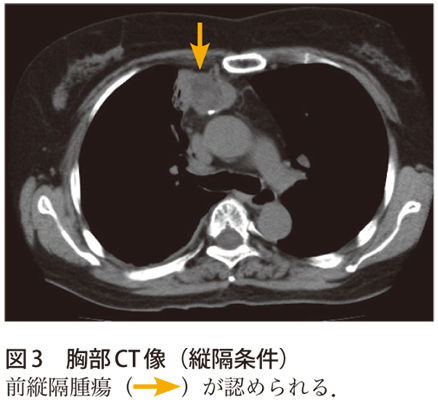

解答 解説 気管支喘息管理中に右背部痛 発熱を訴えた60歳代女性 実践 画像診断q A 羊土社 レジデントノート 実践 画像診断q A 羊土社 レジデントノート 羊土社